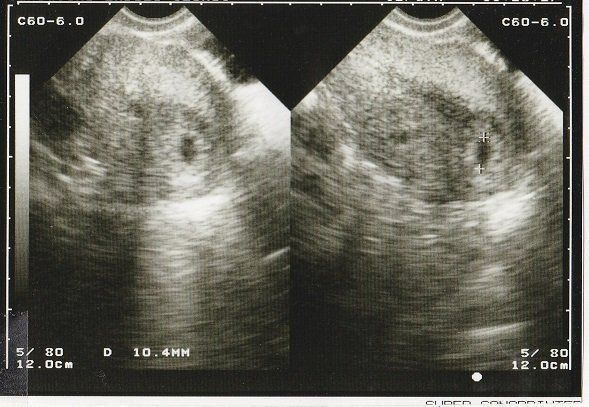

妊娠8週目のエコー写真 10mm以上に成長

CRL(頭殿長=頭からおしりまでの長さ)が10mmを超えました。

順調に大きくなっていますが、まだまだ「大丈夫だろうか?」という不安が大きかった時期。